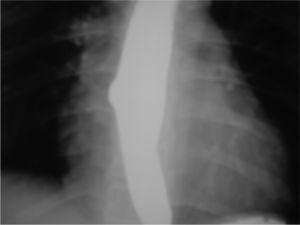

Posteriormente refiere dolor epigástrico por lo que se solicita un tránsito digestivo superior (fig. 1), en el que se aprecia un divertículo esofágico en el tercio medio. La endoscopia demuestra la existencia de dilatación sacular en el tercio medio esofágico. Se practica una manometría encontrando un trastorno motor con diagnóstico de peristalsis esofágica aumentada con ondas de gran amplitud. Después de 3 años de evolución presenta dolor torácico esporádico sin precisar tratamiento por el momento.

Figura 1. Tránsito digestivo superior. Divertículo esofágico en tercio medio.